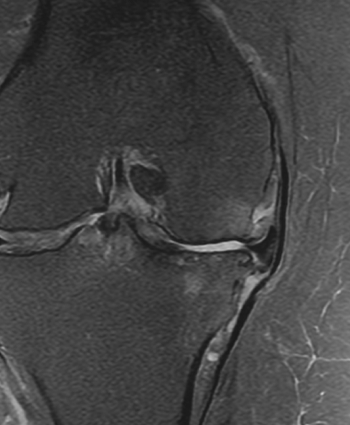

MRI

연골 결손 위치 및 범위,

박리성 병변, 인대 동반 손상 확인